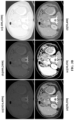

• FIGS. 3A , 3B and 3C depicts CT-slices of chest-region, abdomen-region, and pelvic-region, respectively.

• the FIGS, 3A to 3C clearly demonstrates that by using a greater number of windows, different organs of a particular body-region present in a CT volume, can be highlighted more efficiently.

• using a single window suppresses organ-specific information resulting into a degenerated image-contrast, as shown in FIG. 3A (a), 3B (a) and 3C (a) which in turn makes it hard for the system 100 to learn to focus on various organs present in the given CT volume.